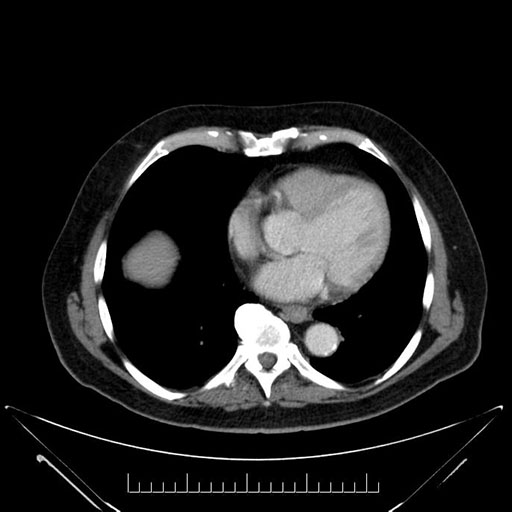

Axial - 3 months prior